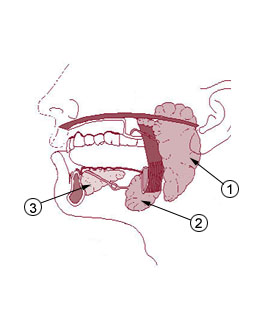

الغدد تحت اللسانية sublingual gland وهي أصغر الغدد اللعابية حجماً بين الغدد اللعابية الثلاث الرئيسية، تقع أسفل مخاط قاعدة الفم. تحتوي على أسناخ مصلية و كثير من الأسناخ المخاطية. وتقع داخل فجوة في عظم الفك السفلي.

- في الأعلى الغشاء الطلائي لقاعدة الفم حيث يبرز مشكلاً نتوءاً.

- في الأسفل العضلة الضرسية اللامية.

- في الأمام الغدة تحت اللسانية النظيرة(حيث تتجاوز نهايتا الغدتين الأماميتان الخط الناصف).

- في الخلف الجزء العميق من الغدة تحت الفكية.